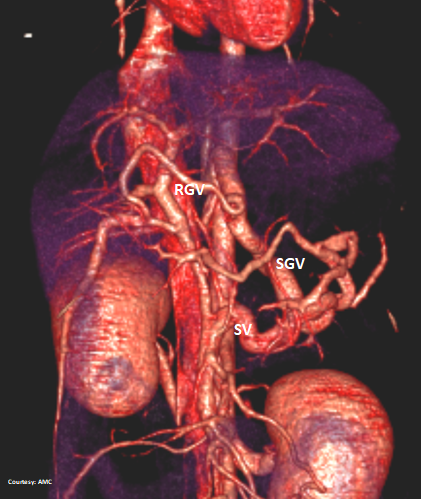

Does the RIGHT GASTRIC VEIN (RGV) contribute blood to the shunt?

Does the SHORT GASTRIC VEIN (SGV) contribute blood to the shunt?